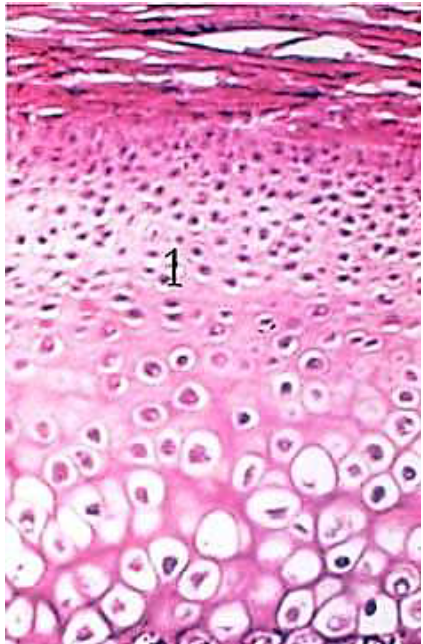

Este é o exemplo de um tecido…

Tecido Conjuntivo Cartilaginoso.